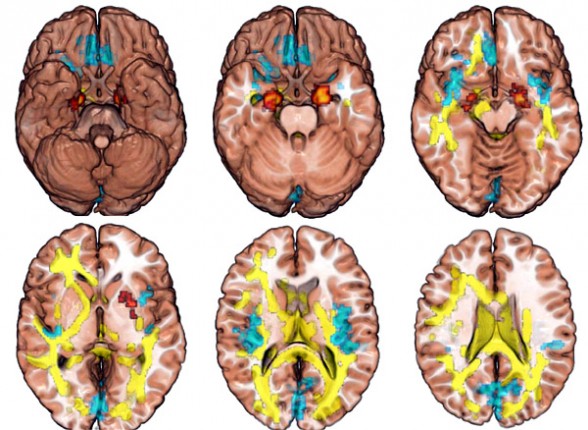

El equipo investigador analizó posteriormente una variedad de imágenes cerebrales en busca de diferencias estructurales entre ambos grupos.

Al analizar las imágenes, identificaron varias diferencias en los sistemas fronto-estratiales del cerebro, que compartían las parejas de hermanos pero no se daban en el resto de participantes.

Estas anormalidades incluyeron un descenso en la densidad de los tractos fibrosos de la sustancia blanca adyacente a la corteza frontal inferior derecha, un incremento en el volumen de materia gris en el putamen y la amígdala, y un descenso en el volumen de materia gris en la ínsula posterior.